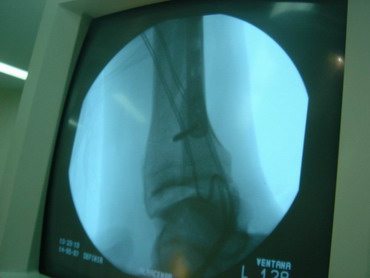

14 - 5 - 07 El torero se interviene hoy a la 12,30 horas en la Clínica Sagrado Corazón de Sevilla. Se confirma diagnóstico provisional hecho en la enfermería de la plaza de Osuna. Fractura de tibia y peroné. Con las siguientes connotaciones: La fractura de peroné es completa y compleja consta de 4 fragmentos diferentes con desplazamiento de los mismos. es decir una fractura conminuta. La tibia presenta fractura maleolar con desplazamiento y además con respecto al tobillo existe una subluxación de la articulación debida a la rotura o explosión de la cápsula articular con desflecamiento de la misma. En resumen un cuadro complejo de tobillo inestable que precisa intervención quirúrgica inmediata. Se estabilizan las fracturas, se sutura la cápsula anterior, se reduce la subuxación, se administran factores de crecimiento y se inmoviliza extremidad. Pronóstico grave. Se estima un tiempo de recuperación de 90 días. Dr. Minguet. Dr. Periañez. Dr. Vaz. Dr. Morales |